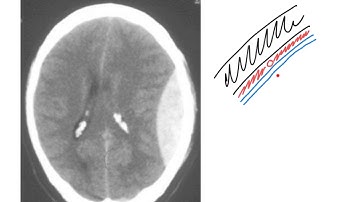

Extradural vs Subdural Haematomas | How do we Diagnose them on CT?